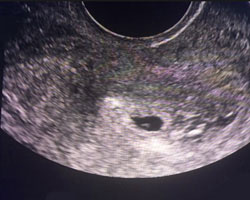

Em seguida vamos mostrar-te um vídeo no qual poderás observar uma gravidez de 5 semanas, bem como uma ecografia do mesmo tempo. É incrível!

Ecografia de 5 semanas